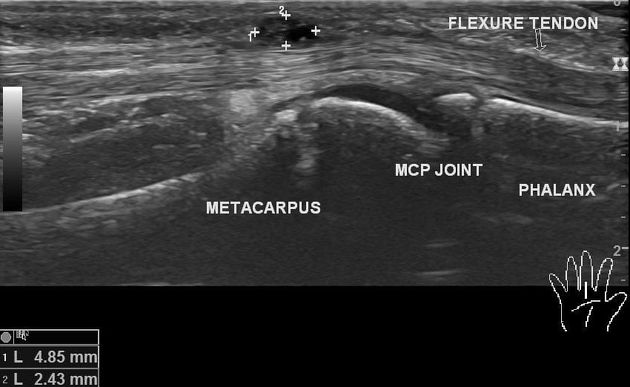

초음파 검사상 건초에서 시작된 손바닥 결절종 @Radiopaedia

마찬가지로

손가락과 발가락의

건초염에서 시작된

결절종은

힘줄과 건초의 염증을

제거해야 하죠.